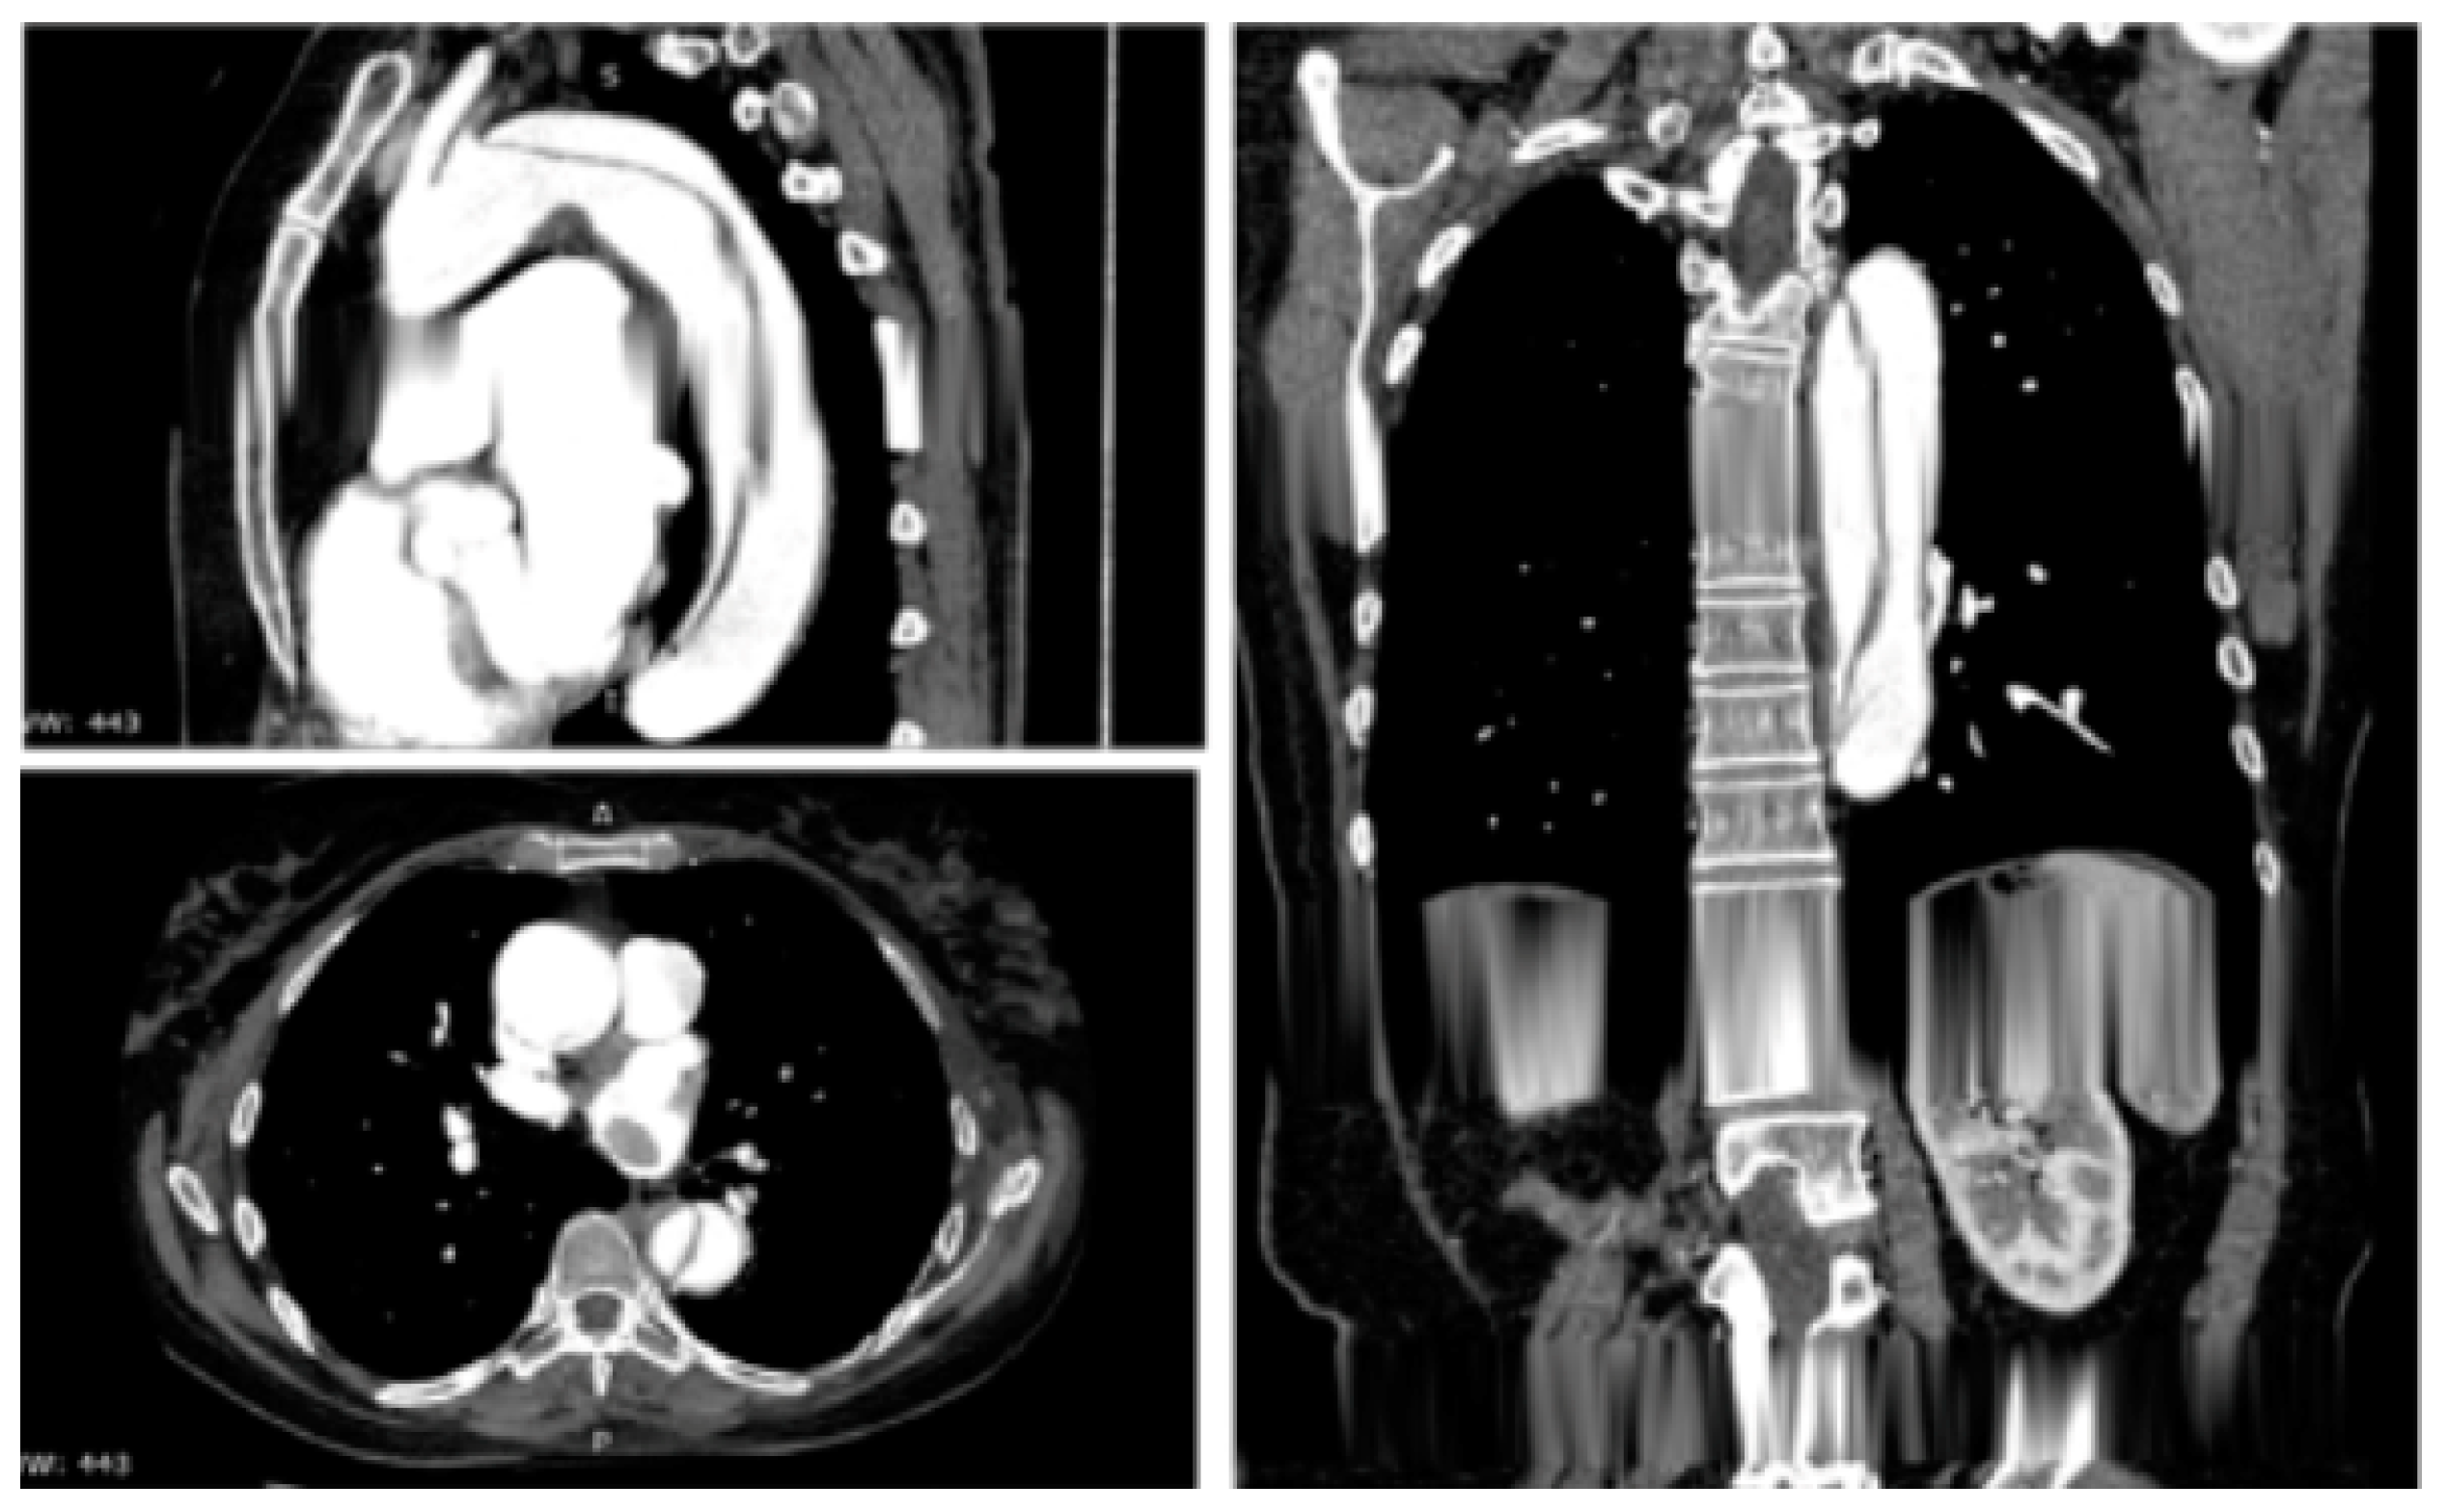

Figure 3.

Contrast-enhanced computed tomography scan reconstruction of type B acute aortic dissection. Reprinted/adapted with permission from Ref. [12]. Copyright year 2020, with permission from Elsevier.